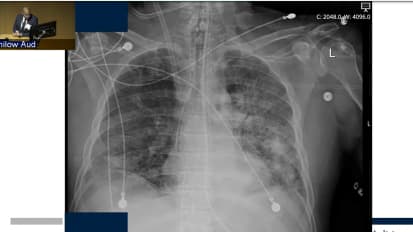

Mobile ECMO for Rescue: Current Status and Regional Experience

In this informative presentation, anesthesiologist and critical care specialist Jacob T Gutsche, MD, examines the origins and progress of the mobile ECMO program at Penn Medicine. In so doing, he describes the incidentals and particulars of the program, including the decision-making process involved for ECMO in the field versus on-site after transport, the risks of injury and recirculation and the indications for VV ECMO at Penn. In analyzing the day-to-day evolution of Penn’s mobile ECMO program, Dr. Gutsche reaches several discerning conclusions. Among these: that deviations from established criteria for inclusion/exclusion and procedural protocols should be avoided; that highly complex care should be centralized by region; that ARDS patients should be stabilized prior to transfer; and that management of VA ECMO requires careful monitoring and nuanced protocols.